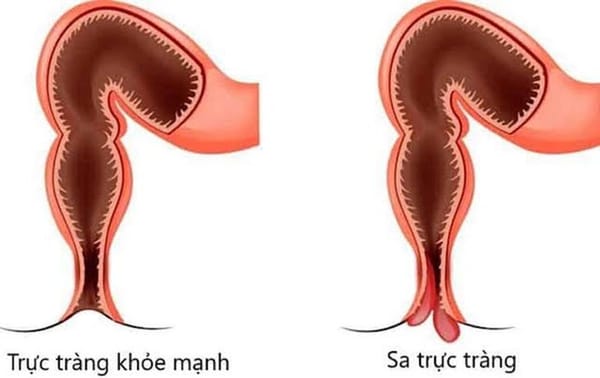

- Phù toàn thân, gan to, lách to: Trẻ xuất hiện phù và gan to do tích tụ mỡ trong cơ thể cũng như nội tạng làm cho bụng to, mất cân đối.

- Đường tiêu hóa: Ảnh hưởng đến gan và tụy làm trẻ kém ăn, đau bụng, tiêu chảy.